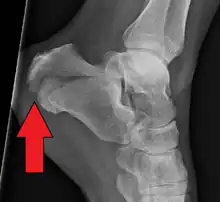

Calcaneal fracture | |

X-ray of a fractured calcaneus | |

Diagnostic method | Based on symptoms, X-rays, CT scan[1] |

Conventional radiography is usually the initial assessment tool when a calcaneal fracture is suspected. Recommended x-ray views are (a) axial, (b) anteroposterior, (c) oblique and (d) views with dorsiflexion and internal rotation of the foot. However, conventional radiography is limited for visualization of calcaneal anatomy, especially at the subtalar joint. A CT scan is currently the imaging study of choice for evaluating calcaneal injury and has substituted conventional radiography in the classification of calcaneal fractures.[13] Axial and coronal views are obtained for proper visualization of the calcaneus, subtalar, calcaneocuboid and talonavicular joints.

The Angle of Gissane, or "Critical Angle", is the angle formed by the downward and upward slopes of the calcaneal superior surface. On a lateral radiograph, an angle of Gissane > 130° suggests fracture of the posterior subtalar joint surface. Böhler's angle, or the "Tuber Angle", is another normal anatomic landmark seen in lateral radiographs. It is formed by the intersection of 1) a line from the highest point of the posterior articular facet to the highest point of the posterior tuberosity, and 2) a line from the former to the highest point on the anterior articular facet. Böhler's angle is normally 25° to 40°.[14] It is named after Austrian physician Lorenz Böhler.[16] A decreased angle is indicative of a calcaneal fracture.